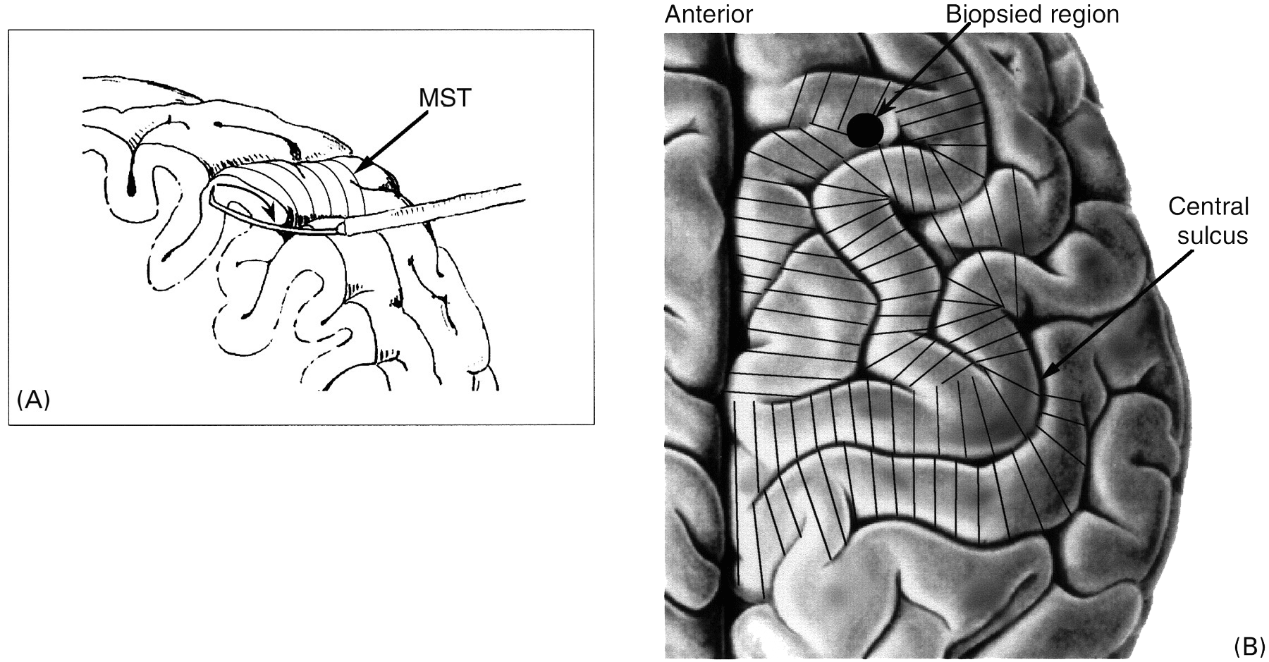

手术方法:

(1)颞叶切除:治疗顽固性颞叶癫痫的一种经典而最常用的手术方法,治疗效果良好。

(2)选择性海马杏仁核切除:多年的经验和研究表明,颞叶内侧结构,尤其是海马杏仁在颞叶癫痫的发生中起着重要的作用。

(3)多处软脑膜下横纤维切断术